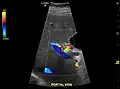

Ultrasound is routinely used in the evaluation of cirrhosis. It may show a small and nodular liver in advanced cirrhosis along with increased echogenicity with irregular appearing areas. Other liver findings suggestive of cirrhosis in imaging are an enlarged caudate lobe, widening of the fissures and enlargement of the spleen. An enlarged spleen (splenomegaly), which normally measures less than 11–12 cm in adults, can be seen and may suggest underlying portal hypertension. Ultrasound may also screen for hepatocellular carcinoma, portal hypertension, and Budd-Chiari syndrome (by assessing flow in the hepatic vein). An increased portal vein pulsatility is an indicator of cirrhosis, but may also be caused by an increased right atrial pressure.[33] Portal vein pulsatility can be quantified by pulsatility indices (PI), where an index above a certain cutoff indicates pathology:

Liver cirrhosis with ascites

Liver cirrhosis with ascites Liver cirrhosis as seen on a CT of the abdomen in transverse orientation

Liver cirrhosis as seen on a CT of the abdomen in transverse orientation caudate lobe hypertrophy in ultrasound due to cirrhosis

caudate lobe hypertrophy in ultrasound due to cirrhosis Hepatofugal flow in portal vein in ultrasound

Hepatofugal flow in portal vein in ultrasound